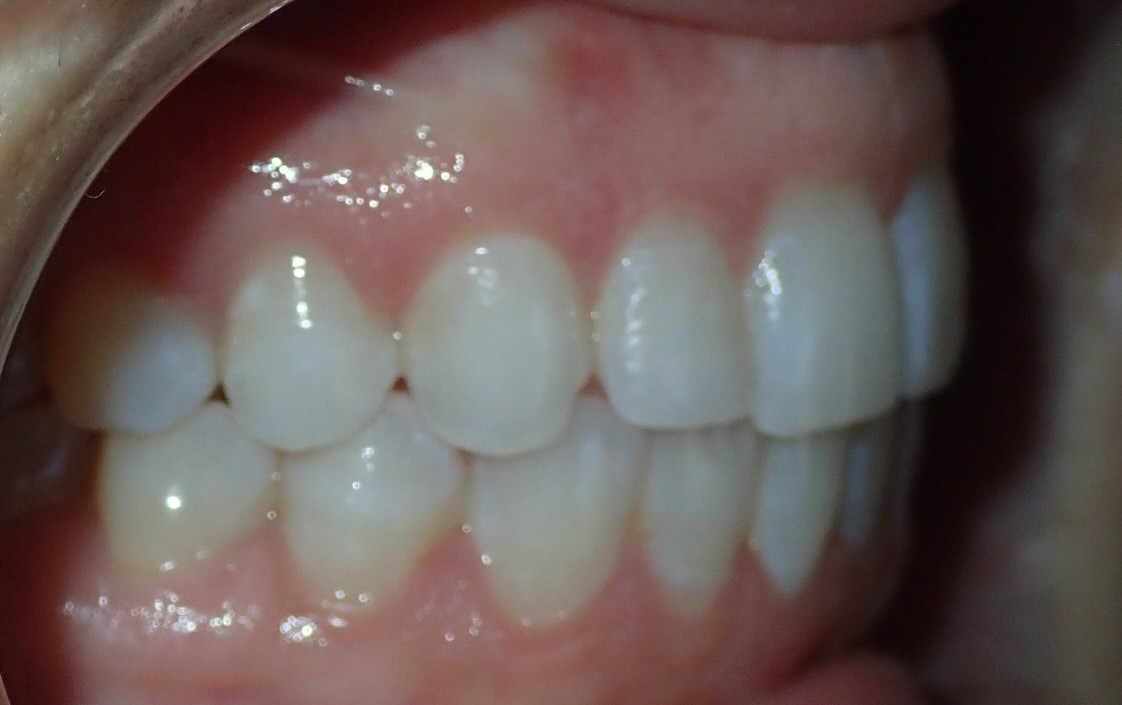

Initial treatment

INTRAORAL